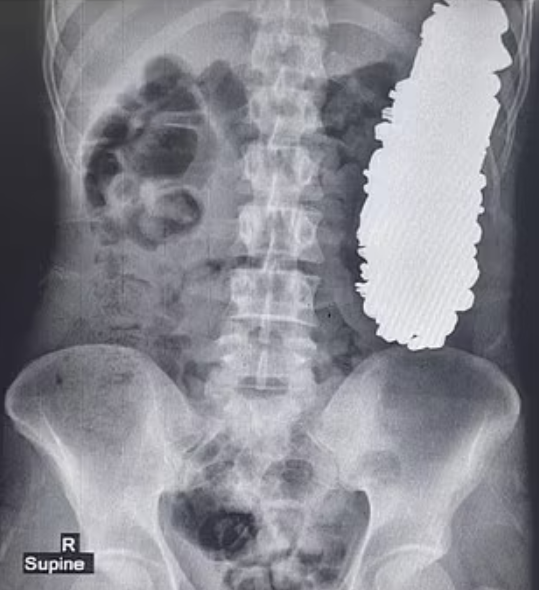

根據《TVBS新聞網》、《鏡週刊》報導,這起離譜案例被刊載於《醫學案例報告雜誌》(Journal of Medical Case Reports)當中,這位37歲的患者因為長期胃部疼痛,加上頻繁嘔吐,使得他完全沒辦法正常吃東西或喝水,於是趕緊到醫院掛急診。醫師替他進行X光檢查後,意外發現患者胃部竟然被超過3公斤的金屬製品塞滿。

醫療團隊隨即為患者安排手術,過程中總共從他體內挖出452件金屬異物,包含螺絲釘、螺帽、各種鑰匙、徽章以及石頭等物品。醫師初步推測,這些東西應該都是患者在過去90天左右陸續吃下肚的,慶幸患者術後復原狀況相當不錯。